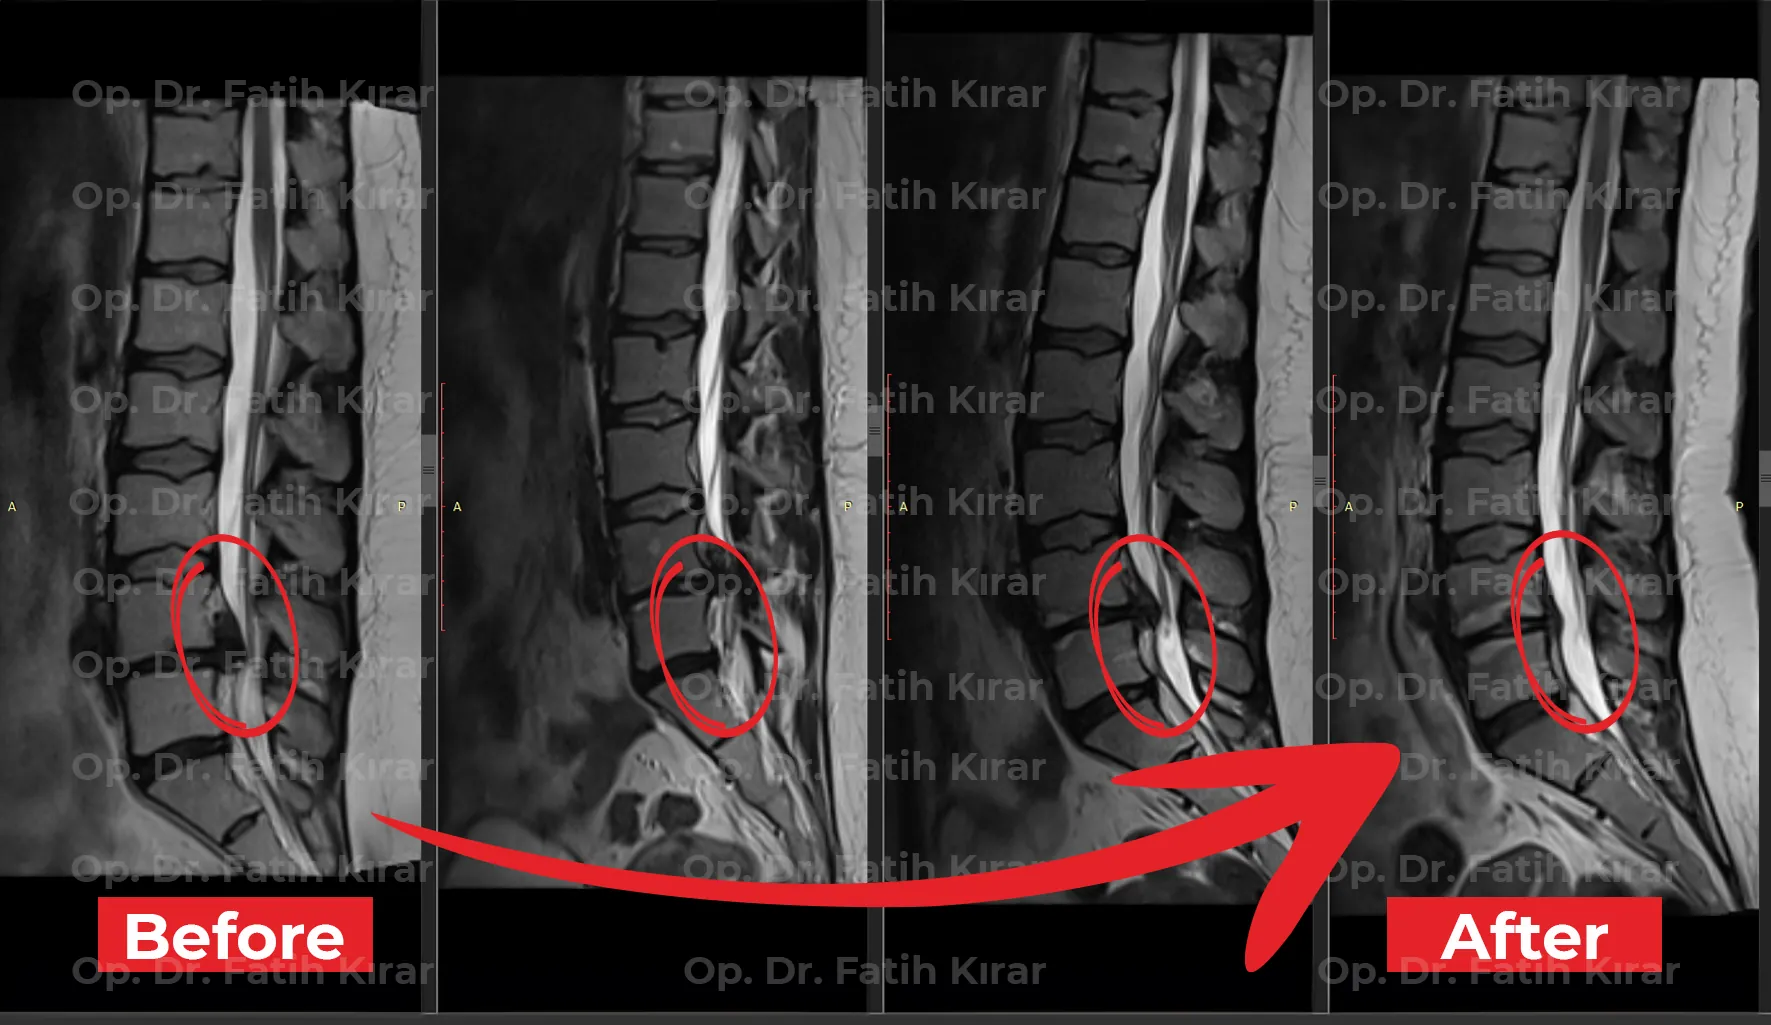

MR Images

Pre and post-treatment MR images of our patients